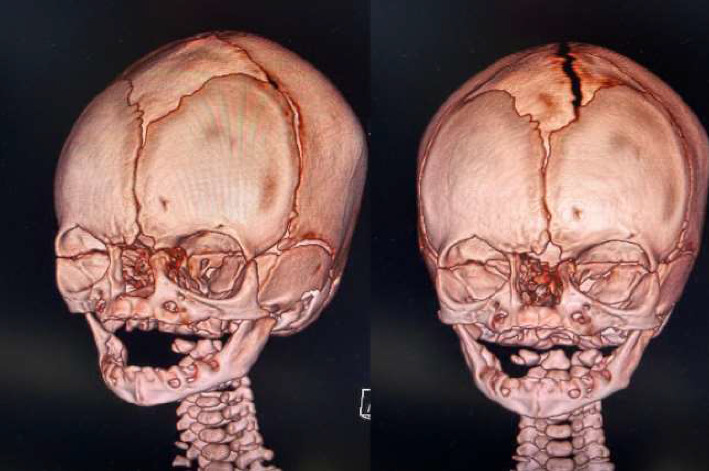

Congenital arhinia and hyporhinia are rare facial anomalies whose knowledge usually comes from case reports. The severity of each case described in literature is variable; it also depends on associated malformations too. Since the newborns are obligate nasal breathers, babies with arhinia or hyporhinia usually have respiratory distress and need airway stabilization. In addition, most of these children present difficulties in feeding and this impairment must be managed early. We describe an unusual case of partial congenital arhinia, the baby did not have other anomalies or any specific complication such as respiratory and feeding issues, so the major problem was the aesthetic and psychological issues for the family. Even if the neonatal course was uncomplicated, a coordinated approach of the pediatrician with the pediatric otolaryngologist, the geneticists and the neurosurgeons was necessary because the management of these malformations is always very complex; due to the lack of reports described in literature, an univocal management and also the best timing and technique for reconstructive surgery are still not defined.